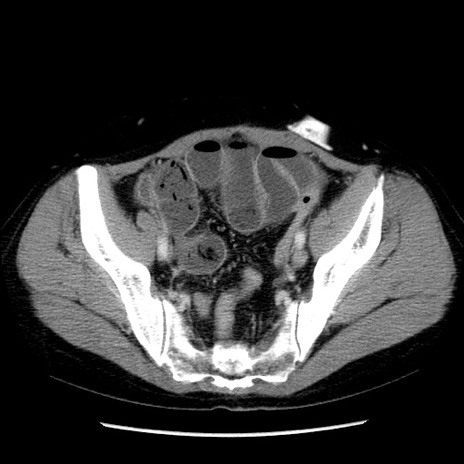

冠状断像

【症例】50歳代女性

【主訴】下腹部痛

【既往歴】卵巣癌術後(8年前に当院で卵巣摘出)

【身体所見】 意識清明、腹部:平坦、腸蠕動音→、やや硬、下腹部自発痛・圧痛あり、反跳痛あり、筋性防御なし。

【データ】WBC 16000、CRP 0.01